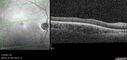

28 year old female Good vision since birth started wearing glasses at 2, denies trauma. She does have congenital nystagmus.

VA OD: Dcc20/200-2 PH20/200 NccJ7

VA OS: Dcc20/160 PHNI NccJ7

IOP: TP: OD:15 OS:12